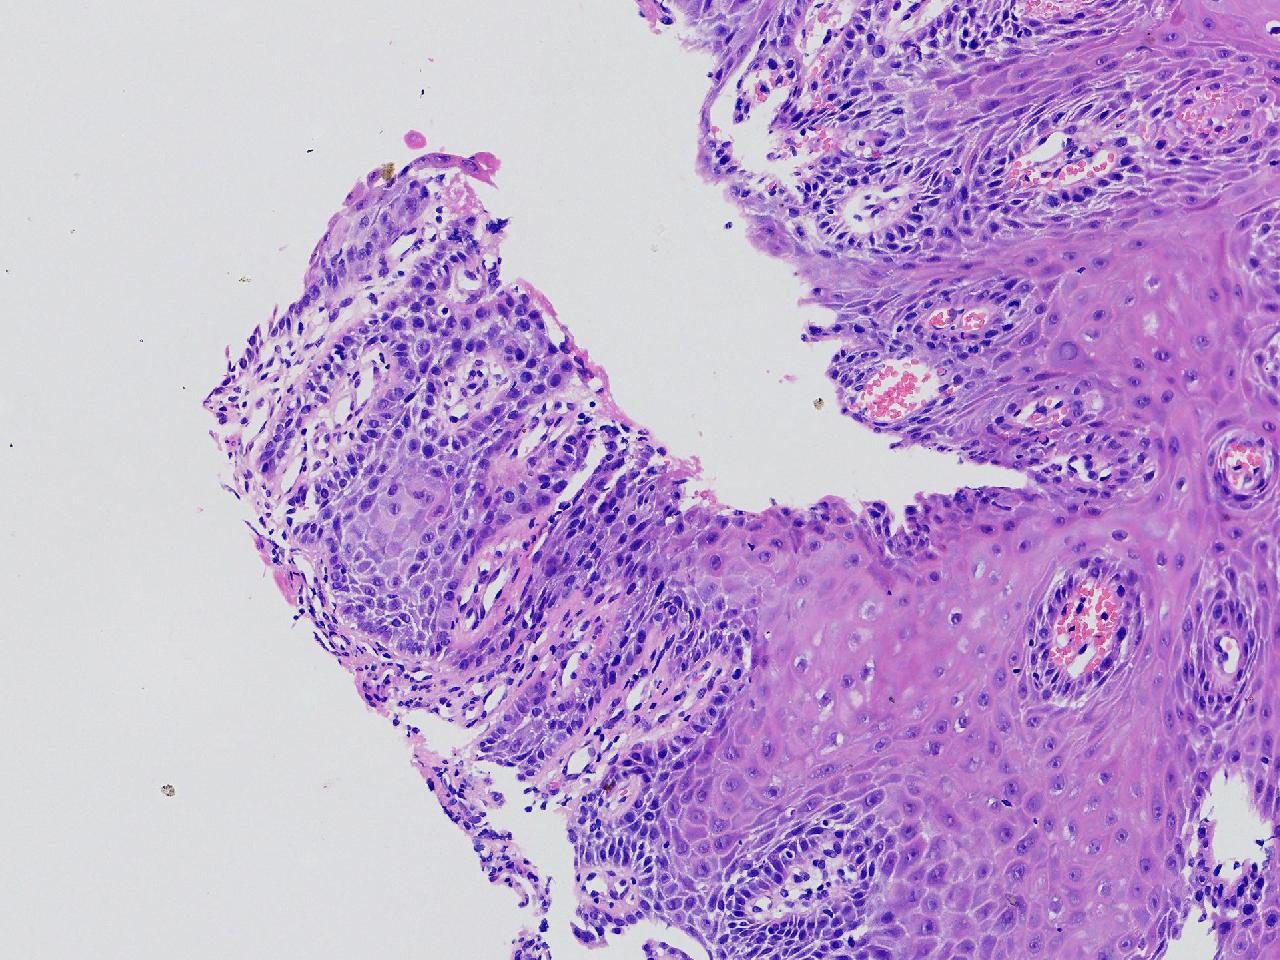

男,62岁,贲门口齿状线上见条状糜烂,活检1块,质软。

贲门口活检

灰白色不整形软组织1块,直径0.2厘米。

图1

鳞皮乳头状增生伴慢性炎。